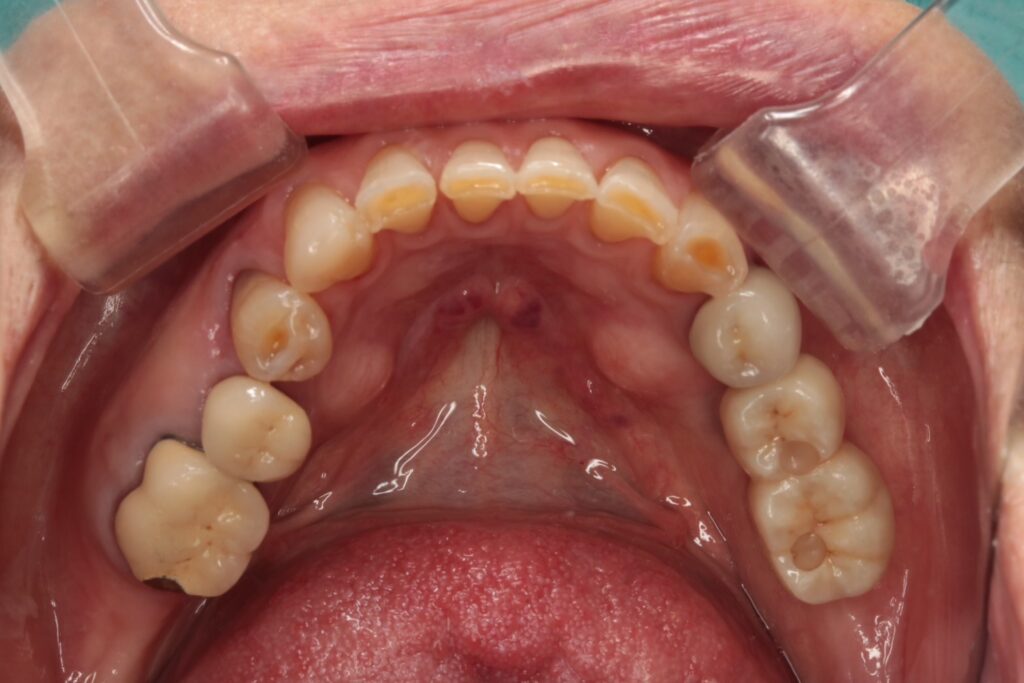

パノラマレントゲンから、上顎・下顎ともに残っている歯が少なく、噛み合わせのバランスも不安定な状態でした。

・上顎:3・3・4・6番のみ残存

・下顎:5・6・7番のみ残存

上顎は残っている歯の位置と本数が少なく、部分入れ歯の維持が不十分で、日常生活に支障が出ている状態でした。